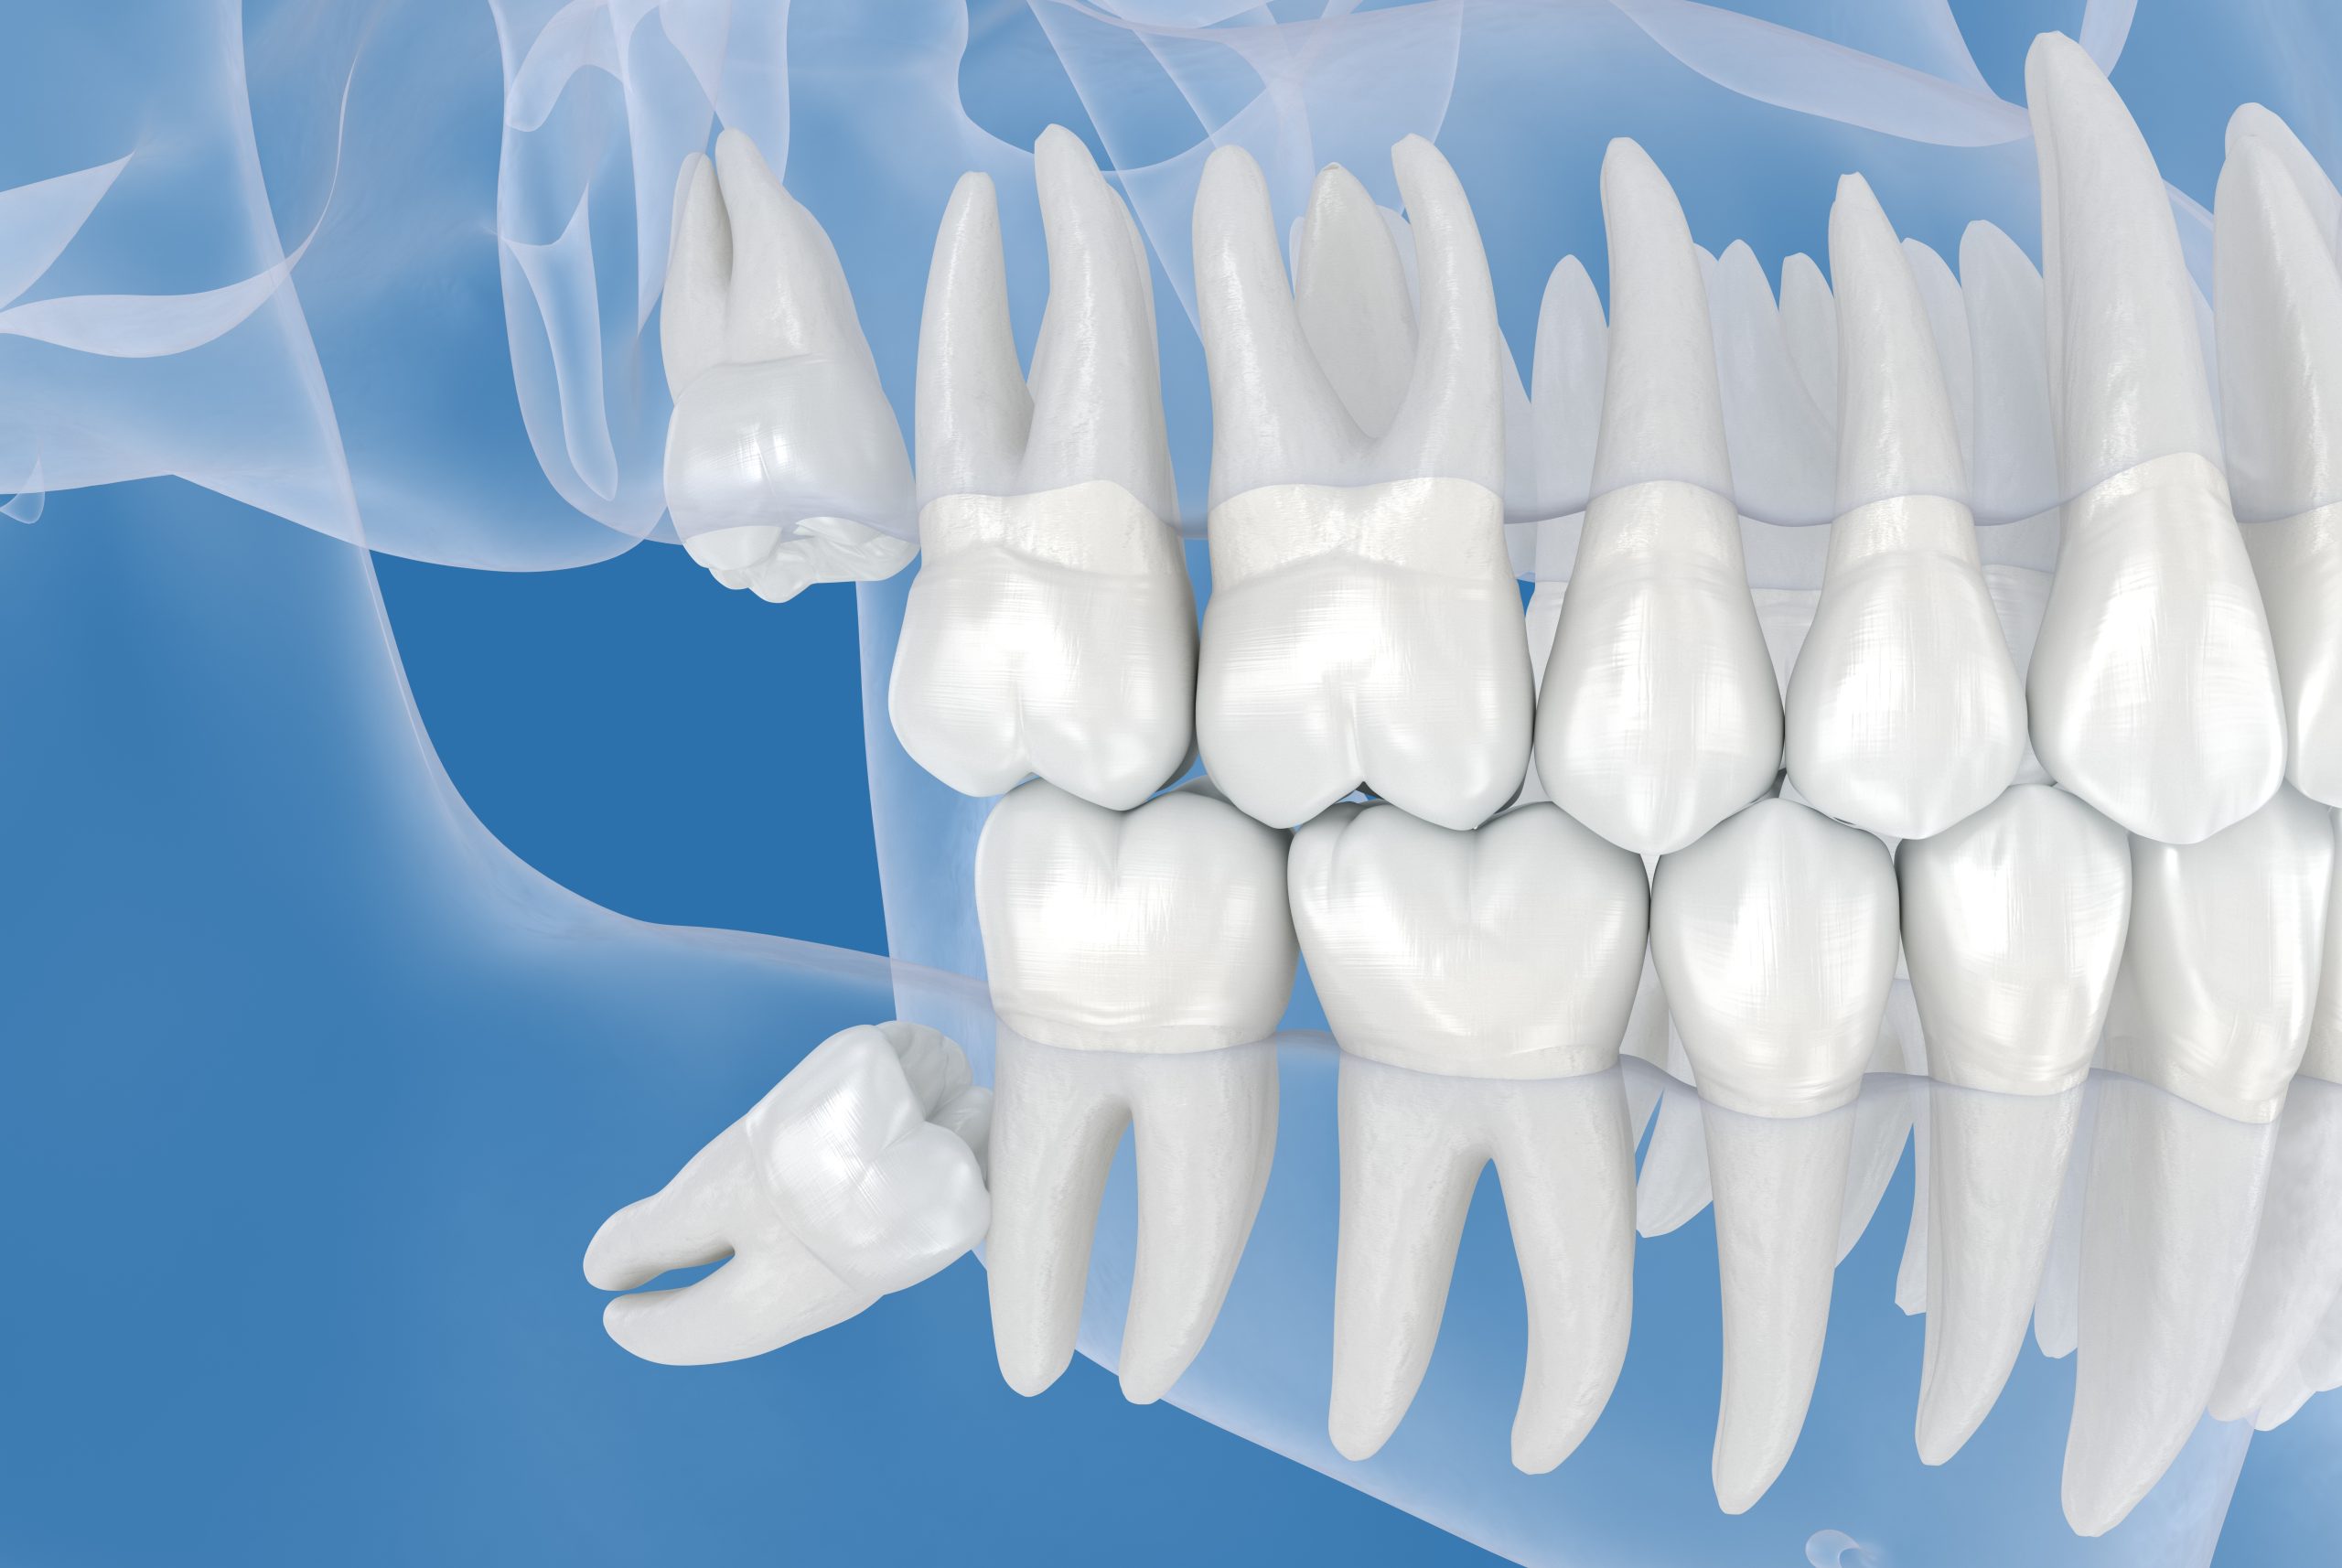

Wisdom teeth are the last set of molars that usually develop in your late teens or early twenties.

In many cases, there is not enough space in the jaw for them to grow properly. This can lead to impaction, infection, or crowding of other teeth.

Wisdom tooth extraction is the process of removing these teeth to prevent or treat these issues.

Unlike regular teeth, wisdom teeth often:

- Grow at an angle or remain trapped under the gums

- Cause swelling or pain

- Lead to infection or gum irritation

- Affect nearby teeth and alignment